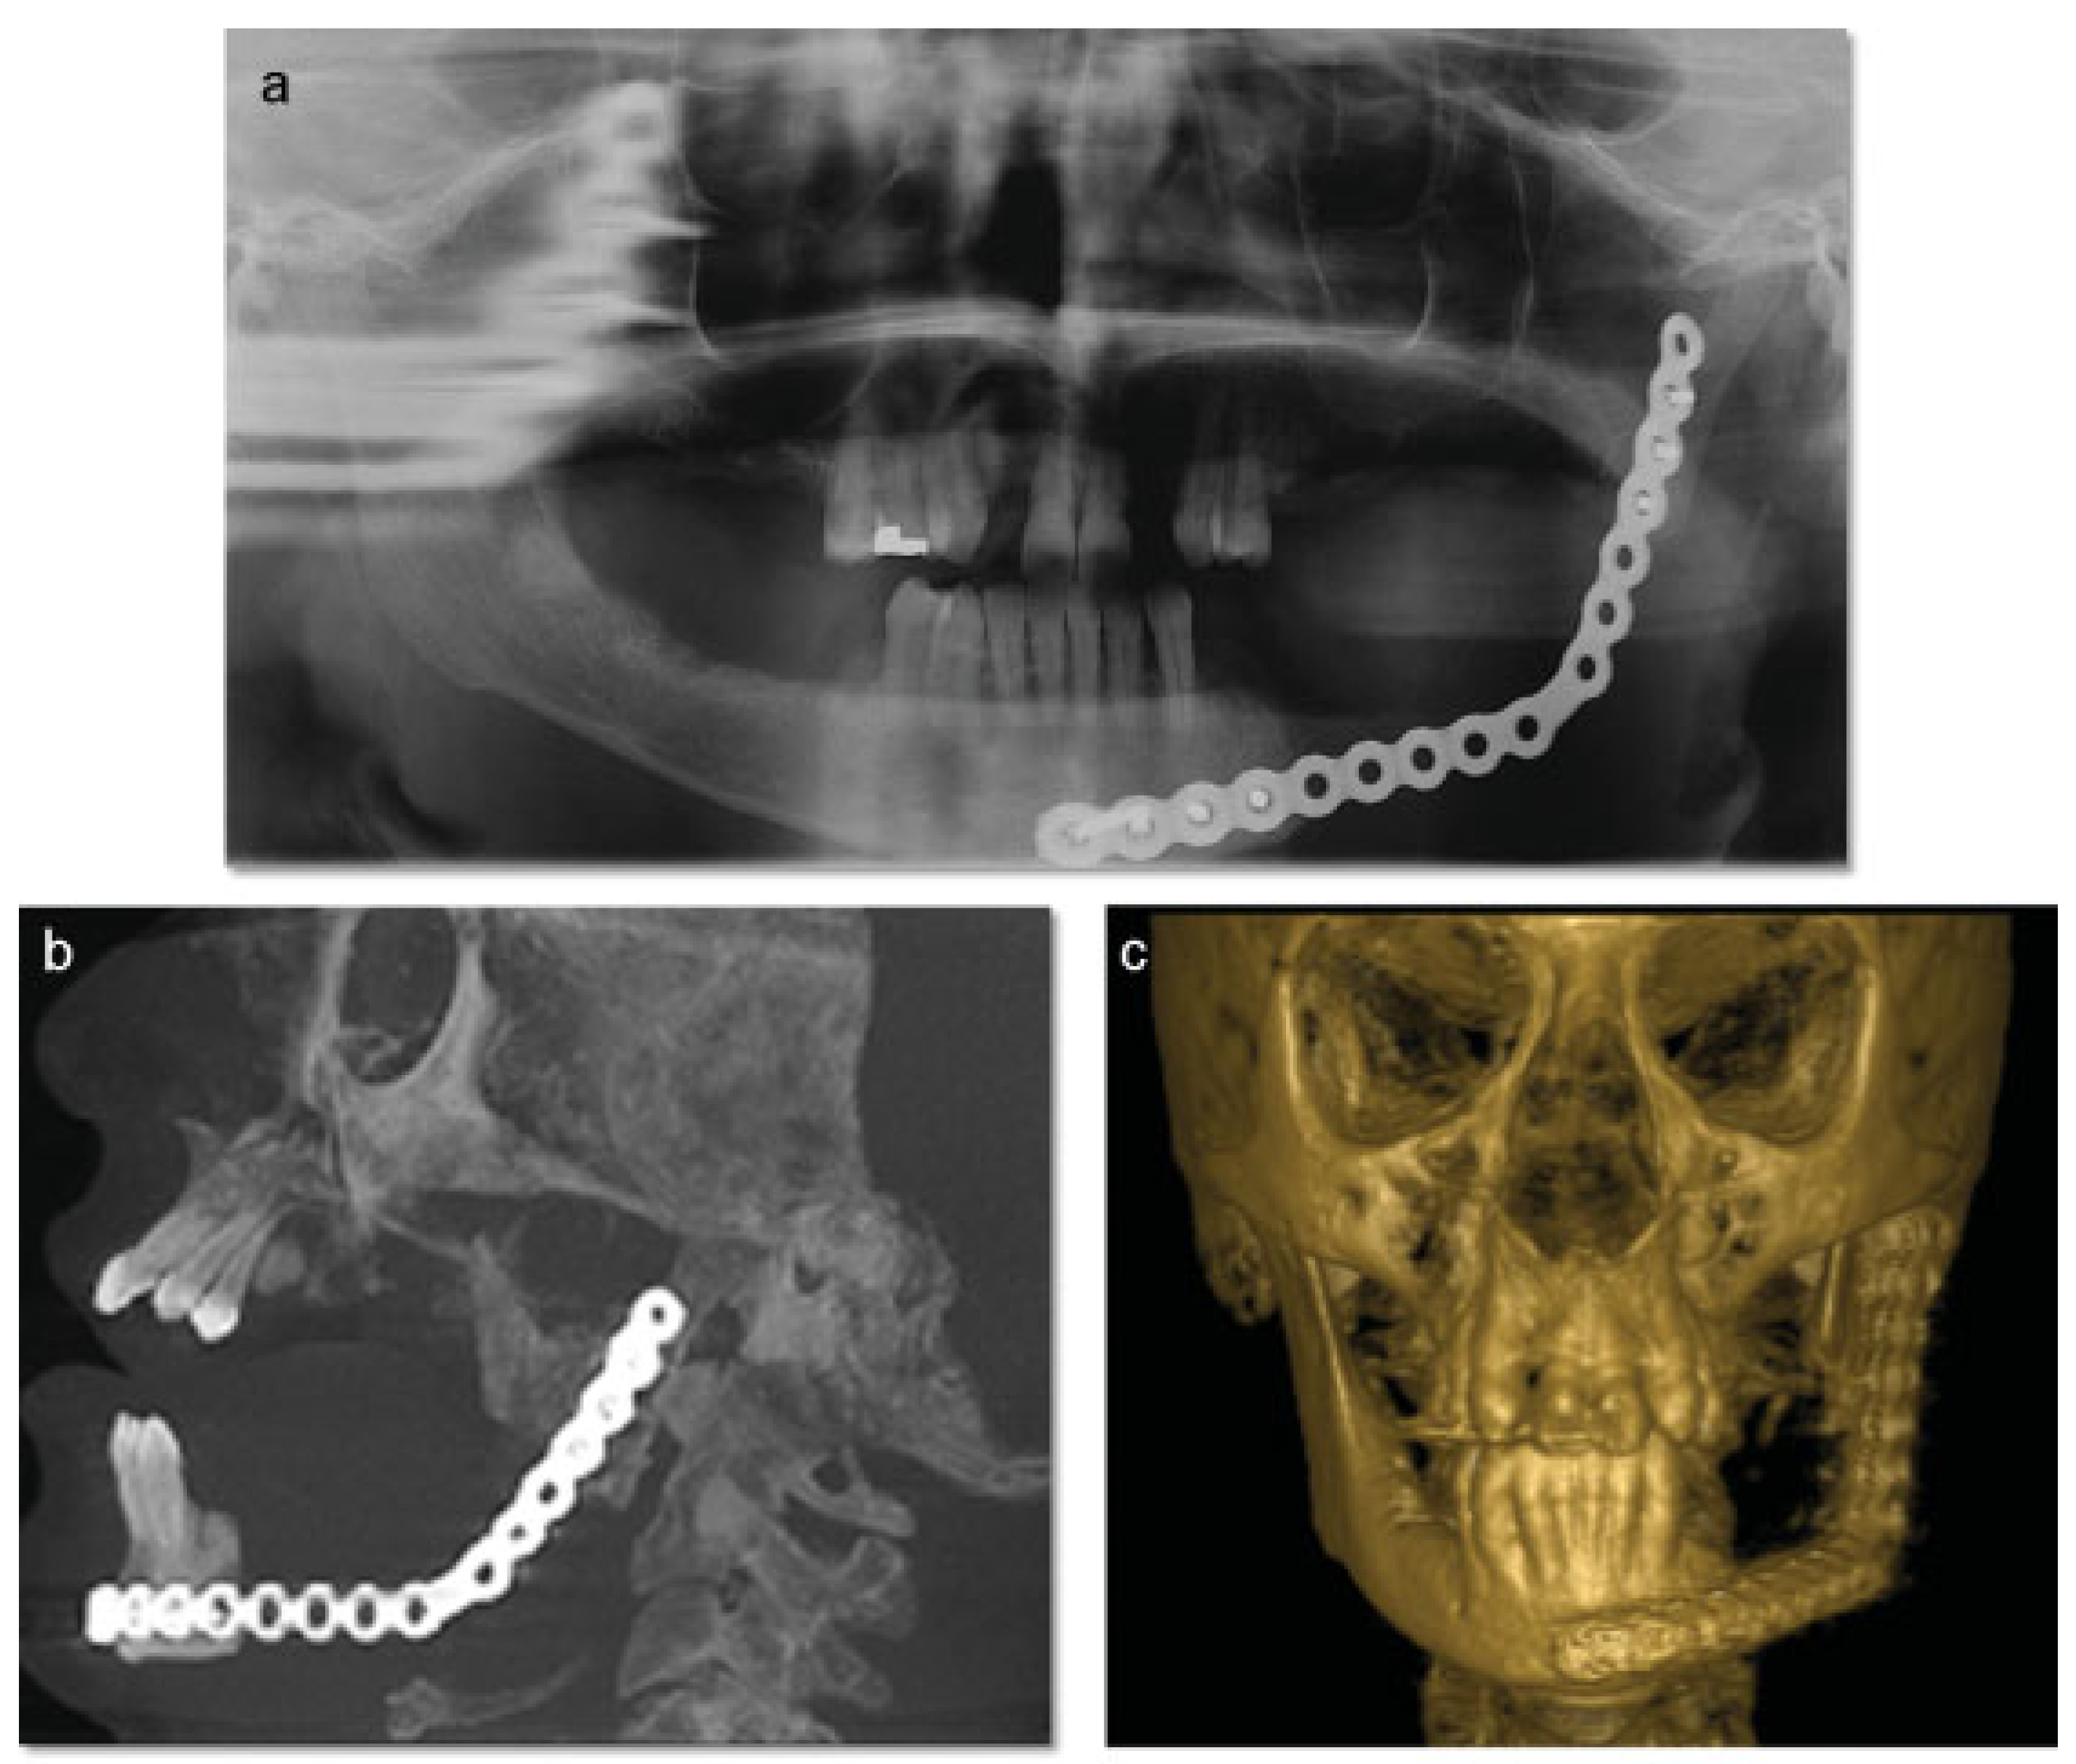

A 46-year-old Caucasian female presented to the Oral Surgery Department at Alameda County Medical Center–Highland General Hospital, complaining of dental pain in maxillary left region for 2 months. Her medical history was significant for hypertension and congestive heart insufficiency for which she takes enalapril, carvedilol, furosemide, and Klor-Con (Klor- Con®, Upsher-Smith Laboratories, Inc., Morristown, NJ) (potassium chloride). She is allergic to codeine. She has a 10 pack- year history of smoking and a remote history of methamphetamine use. Her past surgical history is significant for parathyroid carcinoma, which resulted in primary HTP. She reported that time weight loss, hives, insomnia, fatigue, and bone pain before surgical excision performed 17 years ago. No uterine or kidney lesions were present. She also reported that her brother had a jaw tumor, not surgically treated, because the “jaw growth stopped.” Unfortunately, her brother does not live in the city, and a better investigation concerning his disease could not be performed. Extraoral examination revealed a small swelling in the left mandibular border. Intraorally, the patient presented with poor hygiene with multiple extensive dental caries and periodontal disease. An asymptomatic and firm posterior left mandibular swelling was also present, with buccal and lingual expansion. Radiographic and computed tomography (CT) scan examination revealed a 5-cm mixed radiolucent and radiopaque image in the left mandibular body with well-defined borders and base expansion (Figure 1 and Figure 2a,b). An incisional biopsy was obtained with an intraoral approach which was diagnosed as a benign fibro-osseous lesion, consistent with ossifying fibroma. Initial laboratory analysis prior surgery showed a small increase in serum calcium of 10.5 mg/dL (8.4–10.2 mg/dL). Based on these findings and with the history of parathyroid carcinoma, the patient was referred to an endocrinologist. CT scan of the neck was unequivocal for recurrence and no correction of serum calcium was necessary. The association of ossifying fibroma with primary HPT due parathyroid carcinoma, with a family history of a similar jaw lesion, led to a high suspicion of HPT-JT syndrome. It was extensively discussed with the patient, but she refused to perform any genetic test. Our treatment planning initially included the extraction of the left inferior premolars, which had extensive caries lesions and mobility, performed before the lesion surgical removal. It would enable a better wound closure after resection. Three months later (2010 March), the ossifying fibroma was surgically resected with 5 mm margins (Figure 3) using an intraoral approach, and a 2.4-mm reconstruction plate was placed from the left mandibular ramus to the parasymphysis (Figure 4a–c). The postoperative course was remarkable only for neurosensory disturbance in the left inferior alveolar nerve, which improved but was not completely resolved after 3 years of follow-up. Seven months later (2010 October), using an extraoral approach, the patient underwent a left mandibular reconstruction using her left posterior iliac crest, as well as the right anterior iliac crest. The corticocancellous blocks were secured with 2.4 mm monocortical screws, while cancellous bone chips were inserted between the block grafts (Figure 5a–c). Although regular follow-ups were performed within the first 4 postoperative months, the patient recently returned to the oral surgery clinic for revaluation in 2012. Clinical and radiological examinations (Figure 6) were performed, and oral rehabilitation with dental implants was planned (June 2012). The patient subsequently underwent a third surgical intervention, under local anesthetic and intravenous sedation. The remaining maxillary teeth were extracted, followed by osteoplasty and placement of four implants: two anterior axially placed and two posterior tilted placed. At the same operating time, monocortical screws were from the mandible and three implants were placed in the region of teeth 20, 21, and 28, and alloplastic bone graft was placed covering the exposed threads of the implants (Figure 7a,b). A temporary superior and inferior prostheses were subsequently placed, and a period of 6 months for implant osseointegration before final prosthesis rehabilitation is being observed. The patient is currently followed regularly and, after 3 years of surgical resection, no evidenceof tumor recurrence is seen (Figure 8). Therefore, no evidence of parathyroid carcinoma recurrence is seen after 21 years of endocrinological follow-up.

In terms of treatment, complete excision is recommended although recurrences are uncommon, even after enucleation or curettage [27]. However, due to the mandibular base involvement, large buccal and lingual bone expansion and extensive mobility of the premolars in this case report prompted the decision of surgical resection of the lesion and placement of a 2.4-mm reconstruction plate from the left mandibular ramus to the parasymphysis to preserve the mandibular contour. Mandibular reconstruction with posterior and anterior iliac crest was performed in a second surgical intervention due the possibility of lesion recurrence, even uncommon.

Figure 4. (a) Panoramic radiographic demonstrating the resected area and the 2.4 mm reconstruction plate placed from the left mandibular ramus to the parasymphysis. (b) Sagittal CT scan demonstrating the resected area and the 2.4 mm reconstruction plate placed from the left mandibular ramus to the parasymphysis. (c) 3D-reconstruction CT scan demonstrating the resected area and the 2.4 mm reconstruction plate placed from the left mandibular ramus to the parasymphysis. CT, computed tomography; 3D, three dimensional.